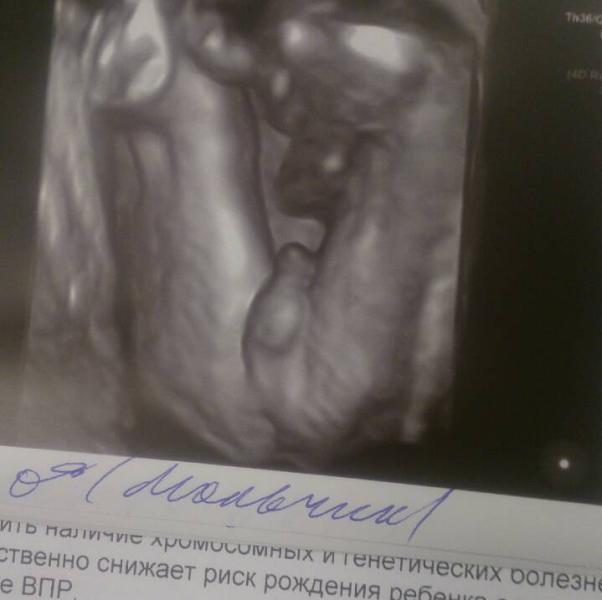

Писюна вам в ленту 😜 И поток эмоций 💓💕💞. Сходила я на УЗИ к Ковальчуку. Я в восторге диком 😊😊😊. Увидела своего малыша сладкого, хоть он и прятал личико в стенку матки 🙈, сбоку углядели все равно (фото не очень четкое даже сделали, Ковальчук старался как мог 👏) а малыш улыбался мне, и головкой мотал 😊. Ну а писюн как всегда на показ первым делом 🙊. Все соответствует сроку и малыш и матка и тд 🙏. Плацента расположена очень высоко, сказал это вообще шикарно. Весим мы 723 гр, рост 27 см 💪👶 (А у ва...